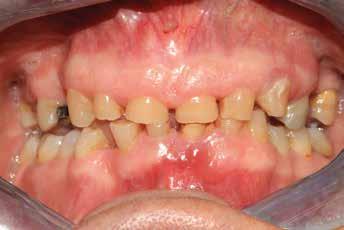

Molto spesso i pazienti sono consci di avere una situazione orale ben lungi dall’essere accettabile. Problemi di salute, propria o di familiari, difficoltà economiche o spese prioritarie da sostenere possono influire in maniera significativa sulla possibilità di curarsi, soprattutto in campo odontoiatrico.

Il paziente del seguente caso, già visitato nel 2019, è poi tornato nel 2021 per una rivalutazione. Già durante la prima visita era stata rilevata una situazione di compromissione generale, sia dal punto di vista igienico, sia funzionale.

Alla visita di rivalutazione è emerso un ulteriore peggioramento della situazione, confermata anche dall’esame radiografico, con parodontopatia, sanguinamento al sondaggio, infiammazione diffusa, alitosi, difetto parodontale verticale mesiale a 2.3, residui radicolari 1.4, 1.6, 1.7, 3.6, 3.8 e carie destruenti di 1.5, 2.6, 3.5, 3.7 (con lesione endoperio) e 4.7 con estrusione e carie (Figg. 1, 2)

Si è consigliato di procedere per gradi, con bonifica di tutti gli elementi malati e irrecuperabili e successivamente sostituire gli elementi mancanti o con protesi rimovibili o con una protesi fissa sostenuta da impianti (Fig. 3).